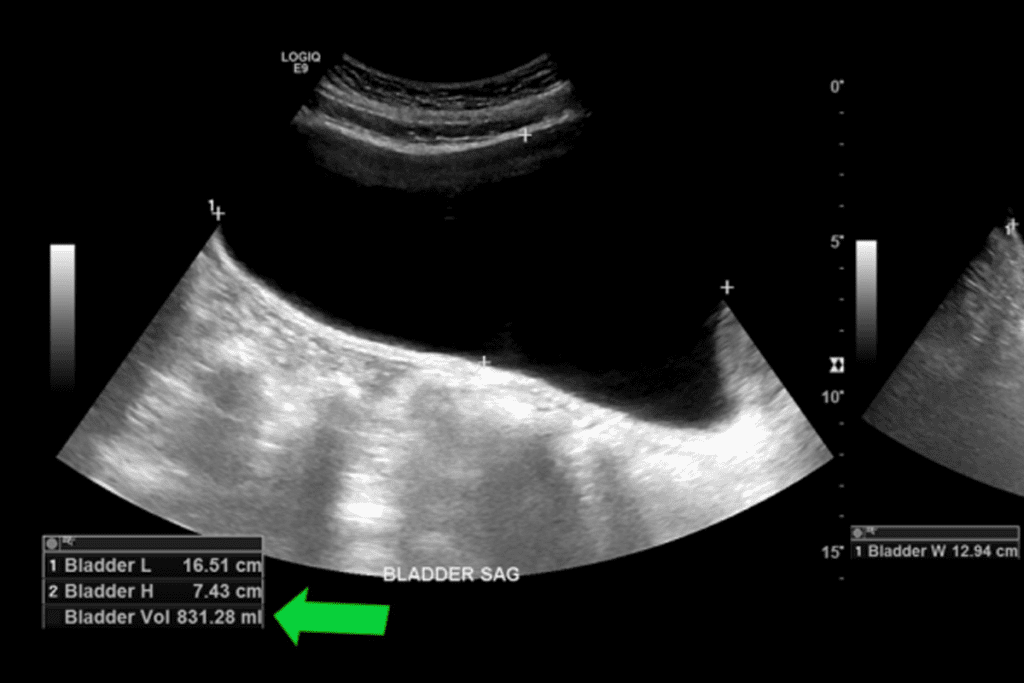

Non-Invasive Bladder Scan Technology

Bladder scan tech has changed how we check post-void residual volume. This method uses ultrasound to guess how full the bladder is. It’s quick and doesn’t hurt. Bladder scans are great for first checks and for people who need to be checked often. The ultrasound technology lets us get the measurements right without needing to use a catheter.

How to Calculate Bladder Volume Accurately

Getting the bladder volume right is key for good PVR measurements. Bladder scan tech uses ultrasound images to figure out the volume. For catheterization, the volume is measured directly. It’s important to follow the right steps and use the right tools to get it right. Accurate calculation of bladder volume is essential for making the right diagnosis and treatment plan.